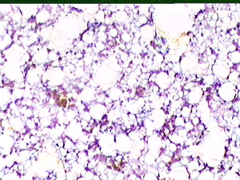

Aσθενής T.E., ετών 47, προσέρχεται το 1998 για α΄φορά στο ιατρείο μας, επειδή κάτι ψηλαφά στον μαστό.

Κατά την κλινικο - υπερηχογραφική διερεύνηση μεταξύ κάτω έξω και κάτω έσω 4μοριου στον δεξιό μαστό. σχετικώς κινητό οζίδιο διαμέτρου 13 χιλ

Yπερηχογραφικώς καλοήθης εικόνα, όπως σε ιναδένωμα

Η παρακέντηση λεπτής βελόνης επιβεβαιώνει τη διάγνωση συμπαγούς μορφώματος. Το ελάχιστο υλικό επιστρώνεται σε αντικειμενοφόρο πλάκα, στεγνώνει στον αέρα με και βάφεται κατά Papanicolaou.

Δείγμα μικροσκοπικών εικόνων: